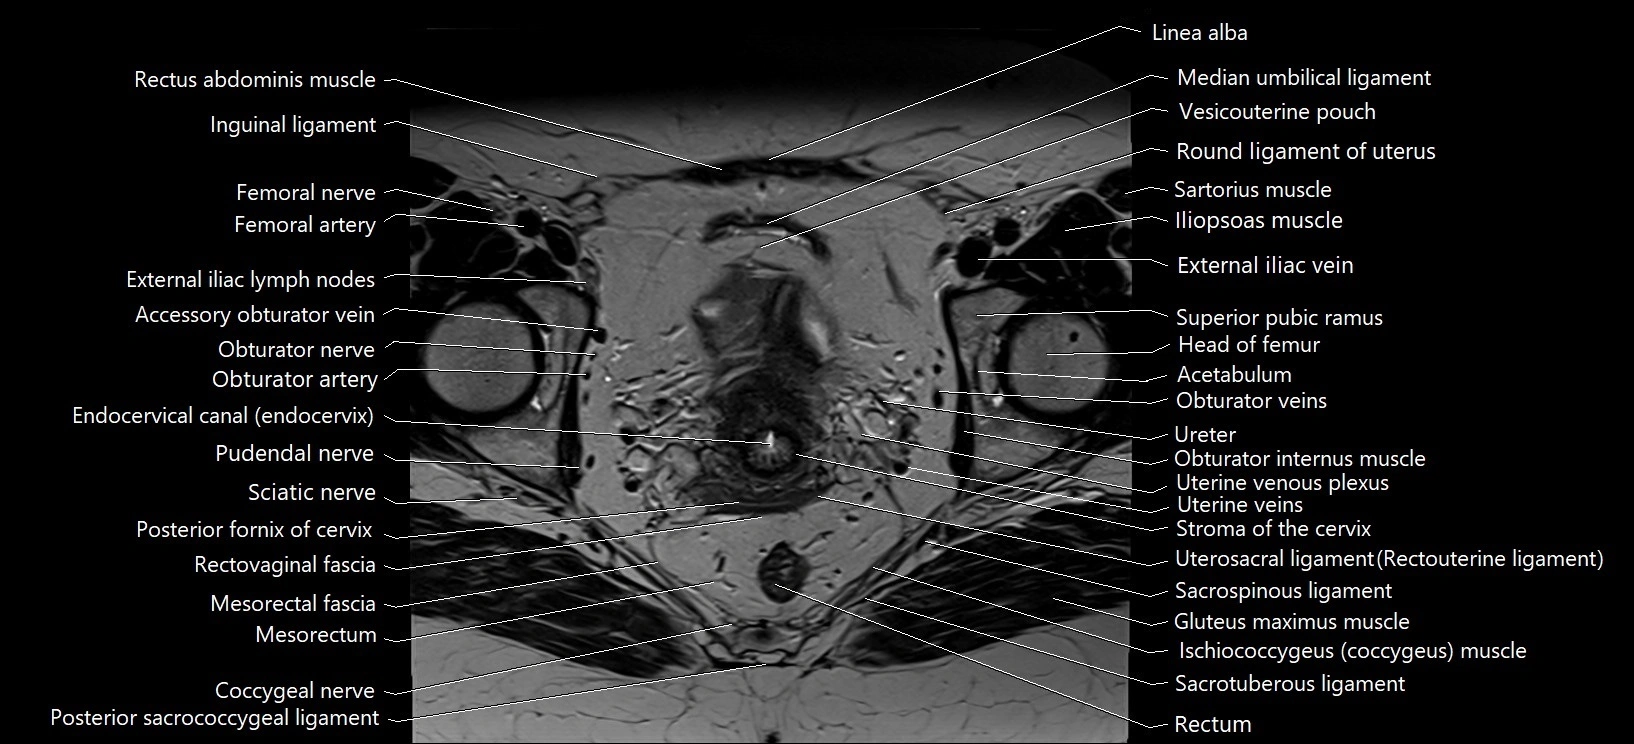

- Accessory obturator artery

- Accessory obturator vein

- Acetabular labrum

- Acetabulum

- Adductor brevis muscle

- Adductor longus muscle

- Adductor minimus muscle

- Coccygeal nerve

- Coccyx

- Endocervical canal

- External iliac lymph nodes

- External iliac vein

- Femoral nerve

- Head of femur

- Iliococcygeus muscle

- Iliopsoas muscle

- Inguinal ligament

- Ischiococcygeus muscle

- Linea alba

- Median umbilical ligament

- Mesorectal fascia

- Mesorectum

- Obturator artery

- Obturator externus muscle

- Obturator internus muscle

- Obturator nerve

- Obturator veins

- Posterior fornix of cervix

- Pudendal nerve

- Rectovaginal septum (rectovaginal fascia)

- Rectum

- Round ligament of uterus

- Sacrospinous ligament

- Sacrotuberous ligament

- Sciatic nerve

- Stroma of the cervix

- Superior pubic ramus

- Uterosacral ligament